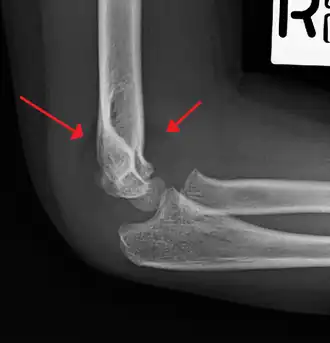

On lateral view of the elbow, there are five radiological features should be looked for: tear drop sign, anterior humeral line, coronoid line, fish-tail sign, and fat pad sign/sail sign (anterior and posterior).[3][8]

Anterior humeral line - It is a line drawn down along the front of the humerus on the lateral view and it should pass through the middle third of the capitulum of the humerus.[9] If it passes through the anterior third of the capitulum, it indicates the posterior displacement of distal fragment.[8]

Fat pad sign/sail sign - A non-displaced fracture can be difficult to identify and a fracture line may not be visible on the X-rays. However, the presence of a joint effusion is helpful in identifying a non-displaced fracture. Bleeding from the fracture expands the joint capsule and is visualized on the lateral view as a darker area anteriorly and posteriorly, and is known as the sail sign.[8]

Coronoid line - A line drawn along the anterior border of the coronoid process of the ulna should touch the anterior part of the lateral condyle of the humerus. If lateral condyle appears posterior to this line, it indicates the posterior displacement of lateral condyle.[8]

Fish-tail sign - The distal fragment is rotated away from the proximal fragment, thus the sharp ends of the proximal fragment looks like a shape of a fish-tail.[8]